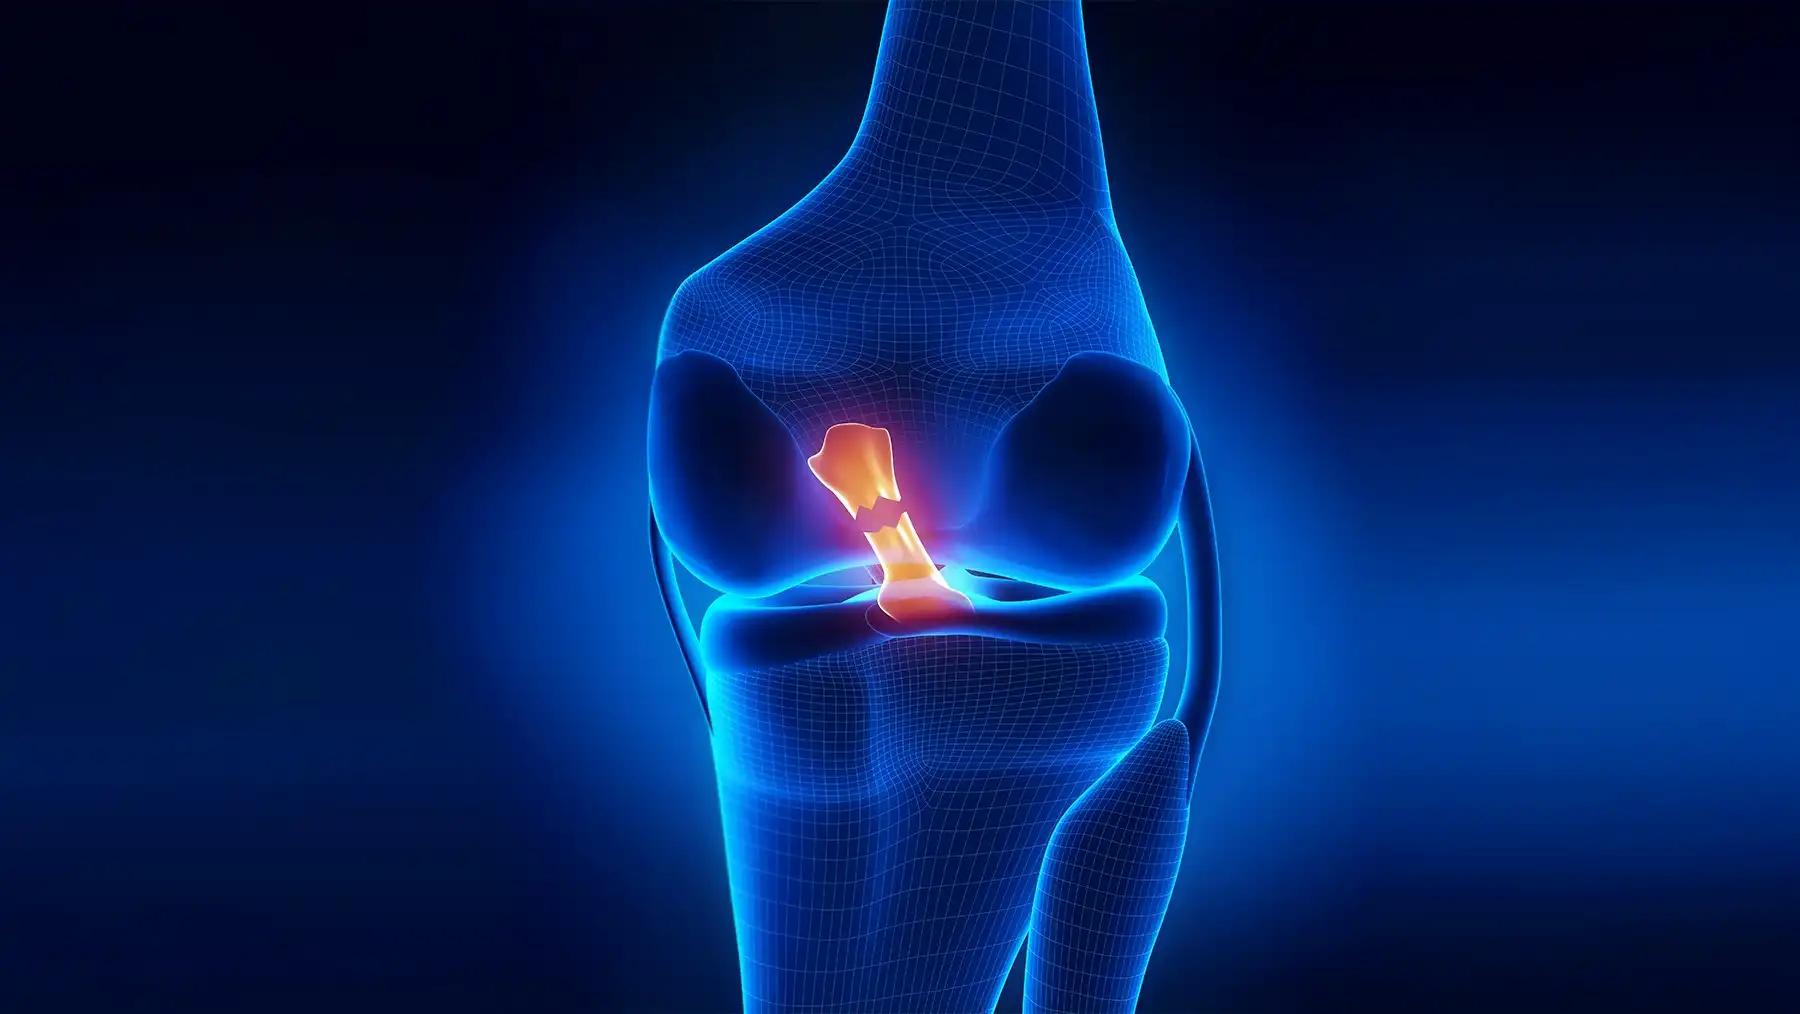

جدیدترین روش ترمیم رباط صلیبی زانو | آرتروسکوپی مدرن 1405 با کمترین درد و سریعترین بهبودی برای تمامی بیماران ادامه مطلب »